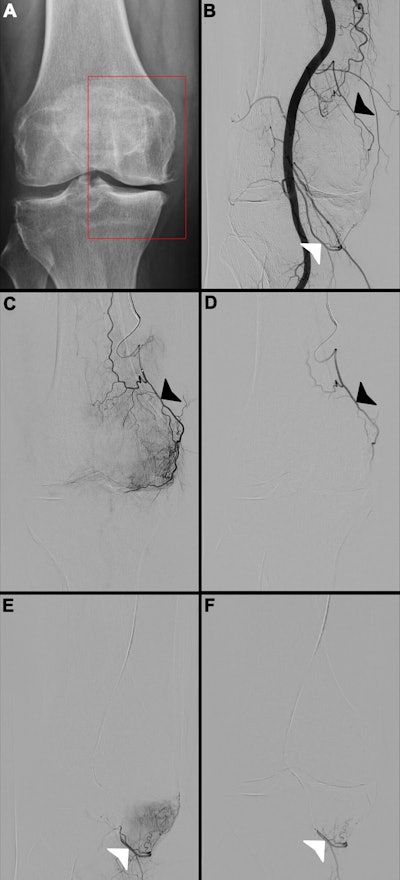

Images in a 65-year-old female patient. (A) Radiograph of the right knee shows Kellgren-Lawrence grade 3 knee osteoarthritis, with chronic pain localized to the medial compartment (red box). (B) Digital subtraction angiogram of the popliteal artery helps identify two potential target arteries: the superior medial genicular artery (black arrowhead) and the inferior medial genicular artery (white arrowhead). (C, E) Selective, pre-embolization digital subtraction angiograms of the superior medial genicular artery (black arrowhead in C) and the inferior medial genicular artery (white arrowhead in E) demonstrate a hyperemic blush in the medial compartment, indicative of pathologic hypervascularity. (D, F) Postembolization digital subtraction angiograms show successful stasis in the superior medial genicular artery (black arrowhead in D) and the inferior medial genicular artery (white arrowhead in F), with complete resolution of the hyperemic blush.Images in a 65-year-old female patient. (A) Radiograph of the right knee shows Kellgren-Lawrence grade 3 knee osteoarthritis, with chronic pain localized to the medial compartment (red box). (B) Digital subtraction angiogram of the popliteal artery helps identify two potential target arteries: the superior medial genicular artery (black arrowhead) and the inferior medial genicular artery (white arrowhead). (C, E) Selective, pre-embolization digital subtraction angiograms of the superior medial genicular artery (black arrowhead in C) and the inferior medial genicular artery (white arrowhead in E) demonstrate a hyperemic blush in the medial compartment, indicative of pathologic hypervascularity. (D, F) Postembolization digital subtraction angiograms show successful stasis in the superior medial genicular artery (black arrowhead in D) and the inferior medial genicular artery (white arrowhead in F), with complete resolution of the hyperemic blush.RSNAEighty patients experienced skin discoloration immediately after the procedure, which resolved completely prior to discharge the following day, and no severe adverse events (grade ≥ 3) were reported.